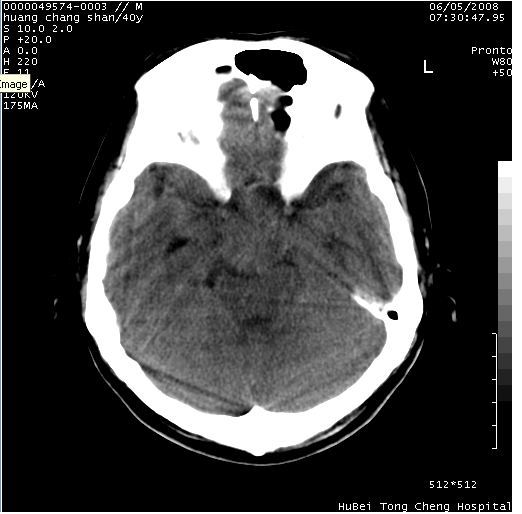

患者 m,40y。头痛,视力模糊,多饮多尿,性欲减退半年余。

行ct平扫+增强,图象如下:

肿瘤强化明显、鞍部骨质结构未见增大、破坏,考虑脑膜瘤可能性大

鞍背无破坏和明显受压,病变明显均匀强化,边界清晰。鞍上区脑膜瘤可能性大,不除外生殖细胞瘤。

平扫病灶呈等密度,增强后强化明显,均匀一致,结合病史首先考虑:垂体瘤。脑膜瘤不支持,因为脑膜瘤平扫多为实性呈均匀高密度影像,内分泌症状多不明显,垂体内分泌素测定正常。

鞍上池肿瘤,鞍背及垂体窝形态变化不明显,病灶强化密度均匀且高度强化,考虑实性颅咽管瘤、生殖细胞瘤及脑膜瘤可能。

1鞍区占位性病变,强化明显,均匀

脑膜瘤>垂体瘤>颅咽管瘤

结合临床考虑鞍上生殖细胞瘤可能性大于脑膜瘤(增强未见脑膜围征),建议结合冠状位扫描看病灶起源及垂体窝、鞍底情况。垂体窝内未见明显软组织密度影,垂体窝未见扩大,暂不考虑垂体瘤;病灶较大,未见囊变及钙化,颅咽管瘤不支持。期待结果!

2、ct表现:肿瘤呈类圆形,均匀略高密度,无囊变,无钙化。侧脑室有扩大。

3、首先考虑:功能性垂体大腺瘤。

4、鉴别诊断:脑膜瘤,瘤体内点状钙化最具特征性,常位于鞍结节。颅咽管瘤,蛋壳样钙化,常有囊变。动脉瘤,位于鞍旁,强化与动脉一致。有时尚需与发生于鞍区的生殖细胞瘤鉴别,生殖细胞瘤钙化亦较常见。